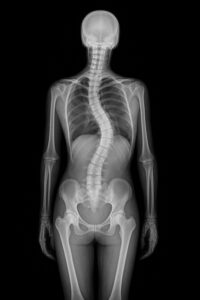

それ、もう背骨が変形し始めてます|若くても起こる背骨変形と腰痛・肩こりの本当の原因

実は最近、20代〜40代の方でも 背骨の変形が静かに始まっている ケースが急増しています。

1. 若い人でも背骨が変形する理由

■「老化だけが原因」は誤解

背骨の変形というと、

「年配の方に起きるもの」と思われがちです。

しかし実際は、

年齢より“使い方の質”で決まるため、

20代・30代でも変形は普通に起こります。

背骨は本来、

S字カーブで衝撃を吸収する仕組みになっています。

しかし、このカーブが崩れると

一点に集中して負荷がかかり、変形が始まります。